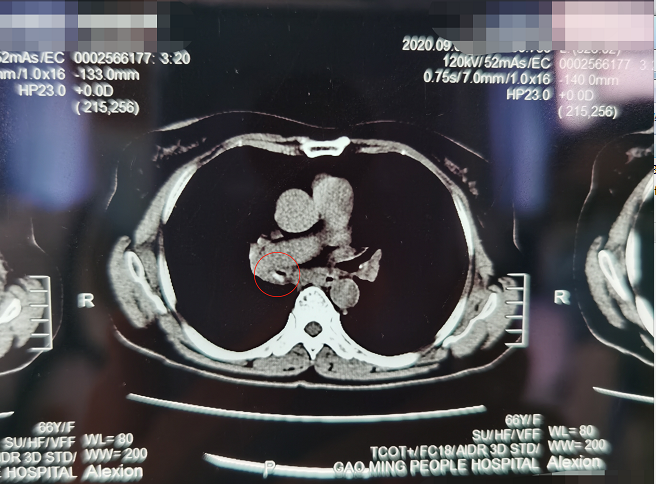

广州市第一人民医院呼吸与危重症医学科就诊魏树全副主任医师仔细看了罗阿姨的肺部CT之后,发现右中间支气管腔内有高密度影。问及病史和个人生活经历,阿姨联想到3年前和家人一次吵架中,口中还嚼着槟榔,想起来可能是当时情绪激动槟榔呛入气道,但是由于当时并无特别明显不适,便没有理会,后来的不间断咳嗽也没有想到是这个原因。